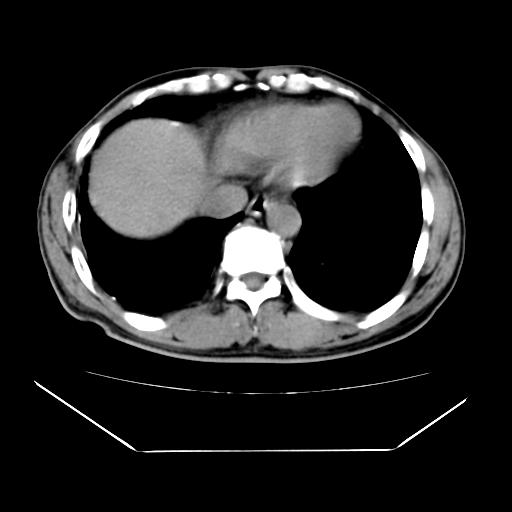

男性,55岁,外院体检afp明显升高,但b超未发现异常,否认乙肝病史。来我院ct增强。有延时扫描。

肝脏右叶动脉期可见低密度影,至延迟期被充填,考虑血管瘤可能性大。

肝右叶病灶

不排除肝右叶肝癌可能。

如果这个是癌灶的话则下腔静脉有瘤栓可能

肝6段血管瘤

血管瘤可能性大。

考虑肝右静脉影。